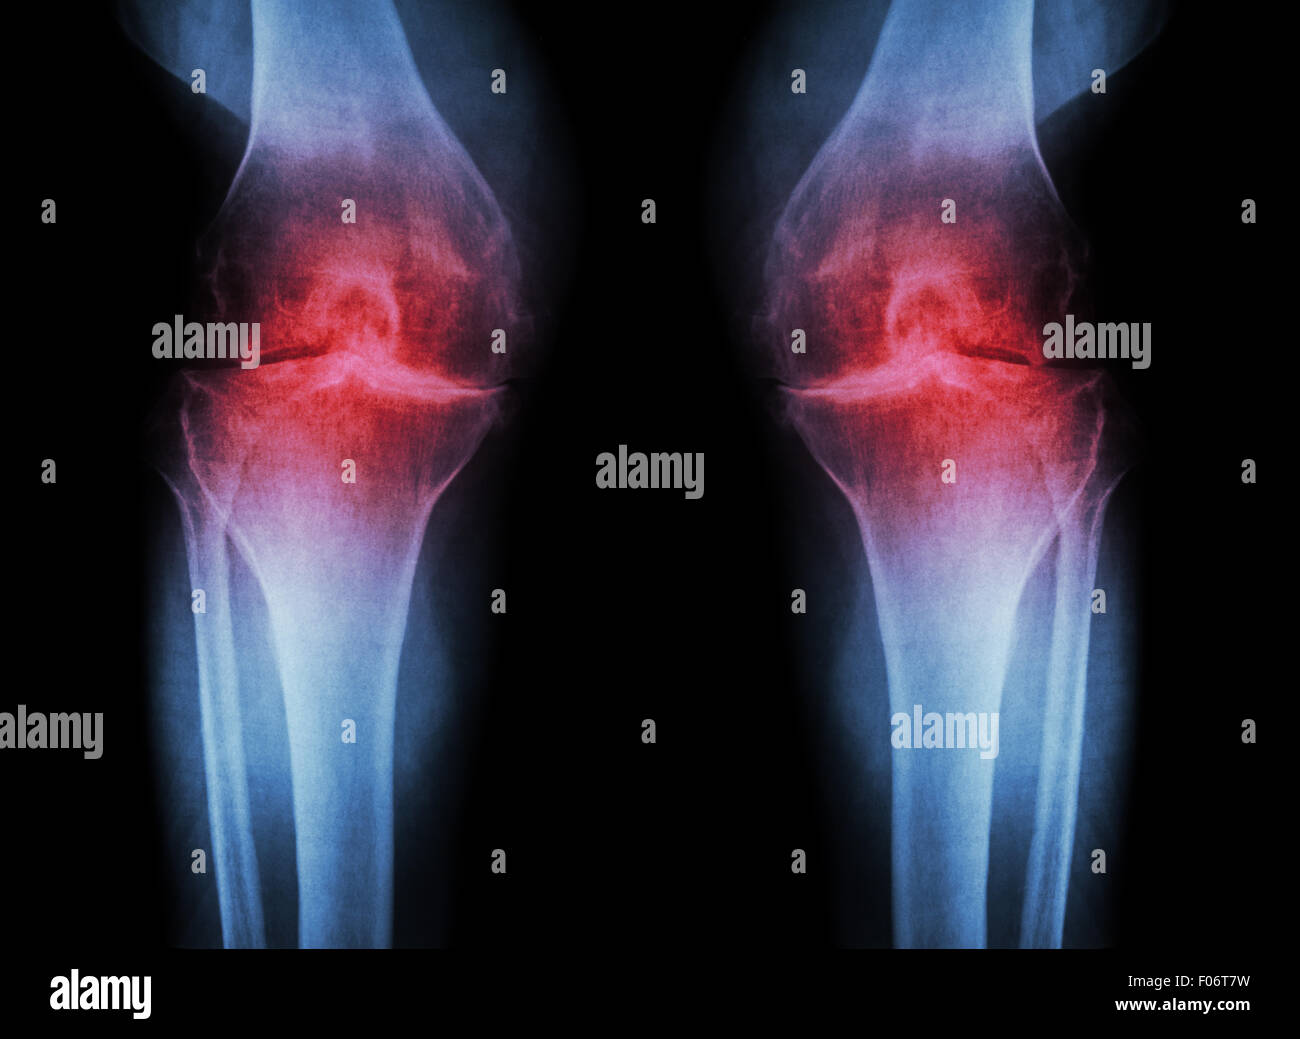

L'ARTHROSE DU GENOU Arthrose du genou ( ) ( Film x-ray à la fois avec l'arthrite du genou d'articulation du genou : articulation du genou espace ) ( Médecine et Sc Banque D'Imageshttps://www.alamyimages.fr/image-license-details/?v=1https://www.alamyimages.fr/photo-image-l-arthrose-du-genou-arthrose-du-genou-film-x-ray-a-la-fois-avec-l-arthrite-du-genou-d-articulation-du-genou-articulation-du-genou-espace-medecine-et-sc-86202589.html

L'ARTHROSE DU GENOU Arthrose du genou ( ) ( Film x-ray à la fois avec l'arthrite du genou d'articulation du genou : articulation du genou espace ) ( Médecine et Sc Banque D'Imageshttps://www.alamyimages.fr/image-license-details/?v=1https://www.alamyimages.fr/photo-image-l-arthrose-du-genou-arthrose-du-genou-film-x-ray-a-la-fois-avec-l-arthrite-du-genou-d-articulation-du-genou-articulation-du-genou-espace-medecine-et-sc-86202589.htmlRFF06T7W–L'ARTHROSE DU GENOU Arthrose du genou ( ) ( Film x-ray à la fois avec l'arthrite du genou d'articulation du genou : articulation du genou espace ) ( Médecine et Sc

L'ARTHROSE DU GENOU Arthrose du genou ( ) ( Film x-ray à la fois avec l'arthrite du genou d'articulation du genou : articulation du genou espace ) ( Médecine et Sc Banque D'Imageshttps://www.alamyimages.fr/image-license-details/?v=1https://www.alamyimages.fr/photo-image-l-arthrose-du-genou-arthrose-du-genou-film-x-ray-a-la-fois-avec-l-arthrite-du-genou-d-articulation-du-genou-articulation-du-genou-espace-medecine-et-sc-86202573.html

L'ARTHROSE DU GENOU Arthrose du genou ( ) ( Film x-ray à la fois avec l'arthrite du genou d'articulation du genou : articulation du genou espace ) ( Médecine et Sc Banque D'Imageshttps://www.alamyimages.fr/image-license-details/?v=1https://www.alamyimages.fr/photo-image-l-arthrose-du-genou-arthrose-du-genou-film-x-ray-a-la-fois-avec-l-arthrite-du-genou-d-articulation-du-genou-articulation-du-genou-espace-medecine-et-sc-86202573.htmlRFF06T79–L'ARTHROSE DU GENOU Arthrose du genou ( ) ( Film x-ray à la fois avec l'arthrite du genou d'articulation du genou : articulation du genou espace ) ( Médecine et Sc

L'ARTHROSE DU GENOU Arthrose du genou ( ) ( Film x-ray à la fois avec l'arthrite du genou d'articulation du genou : articulation du genou espace ) ( Médecine et Sc Banque D'Imageshttps://www.alamyimages.fr/image-license-details/?v=1https://www.alamyimages.fr/photo-image-l-arthrose-du-genou-arthrose-du-genou-film-x-ray-a-la-fois-avec-l-arthrite-du-genou-d-articulation-du-genou-articulation-du-genou-espace-medecine-et-sc-86202580.html

L'ARTHROSE DU GENOU Arthrose du genou ( ) ( Film x-ray à la fois avec l'arthrite du genou d'articulation du genou : articulation du genou espace ) ( Médecine et Sc Banque D'Imageshttps://www.alamyimages.fr/image-license-details/?v=1https://www.alamyimages.fr/photo-image-l-arthrose-du-genou-arthrose-du-genou-film-x-ray-a-la-fois-avec-l-arthrite-du-genou-d-articulation-du-genou-articulation-du-genou-espace-medecine-et-sc-86202580.htmlRFF06T7G–L'ARTHROSE DU GENOU Arthrose du genou ( ) ( Film x-ray à la fois avec l'arthrite du genou d'articulation du genou : articulation du genou espace ) ( Médecine et Sc